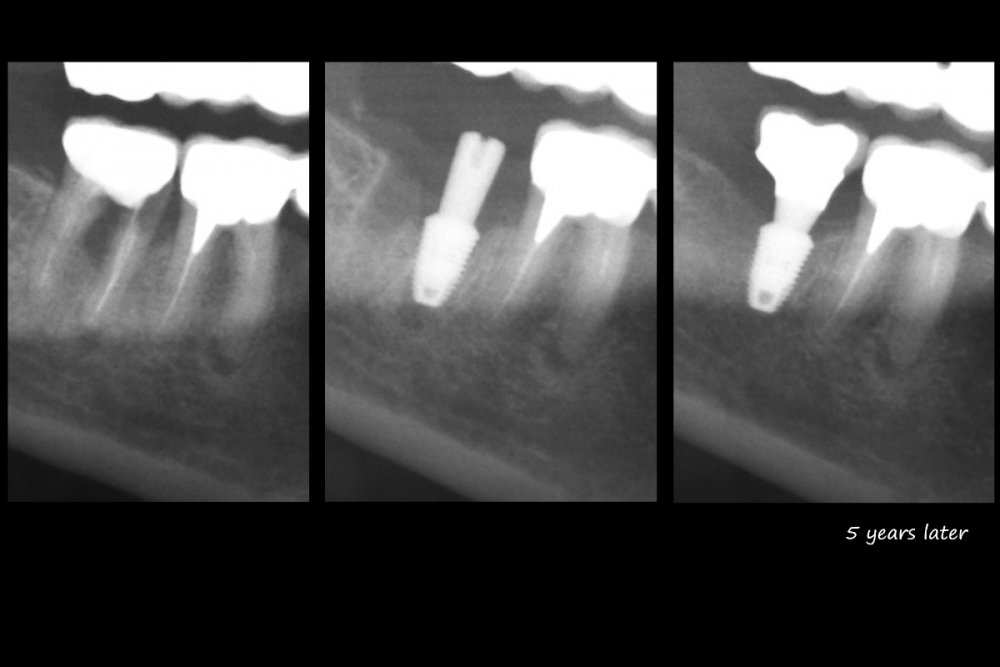

Irouil Опубликовано 10 мая, 2021 Поделиться Опубликовано 10 мая, 2021 1 час назад, Карен Аванесов сказал: Я. Тогда позволю себе ещё один вопрос? Почему такой резкий переход дистально из вертикальной в горизонтальную плоскость? Там вроде не было твёрдых тканей, которые надо было обходить. Ссылка на комментарий

Карен Аванесов Опубликовано 11 мая, 2021 Автор Поделиться Опубликовано 11 мая, 2021 19 часов назад, Irouil сказал: Тогда позволю себе ещё один вопрос? Почему такой резкий переход дистально из вертикальной в горизонтальную плоскость? Там вроде не было твёрдых тканей, которые надо было обходить. Было много плотных мягких тканей, формирователь тонкий, временной коронки не было, да и не тот случай. Самое главное, все быстро фиксируется, без анестезии, без сдавливания и последующих жалоб от пациентов. Ссылка на комментарий